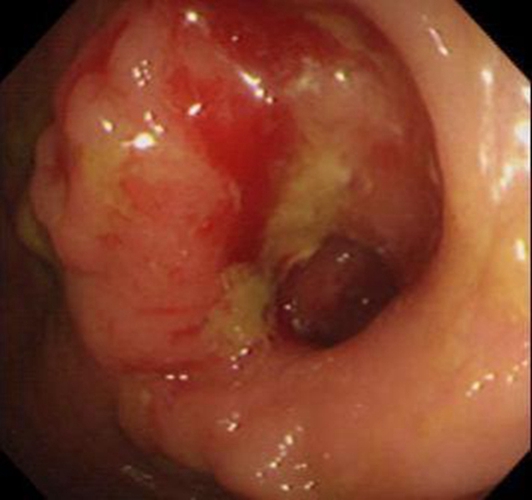

乙狀結腸癌潰瘍型症狀

乙狀結腸癌未分化癌早期 症狀